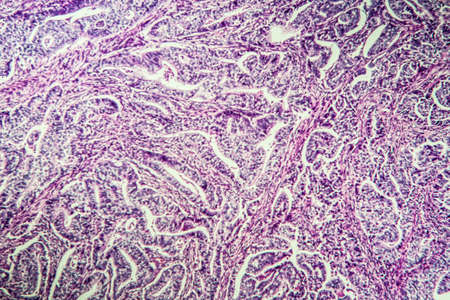

Breast cancer of the woman diseased tissue 100x